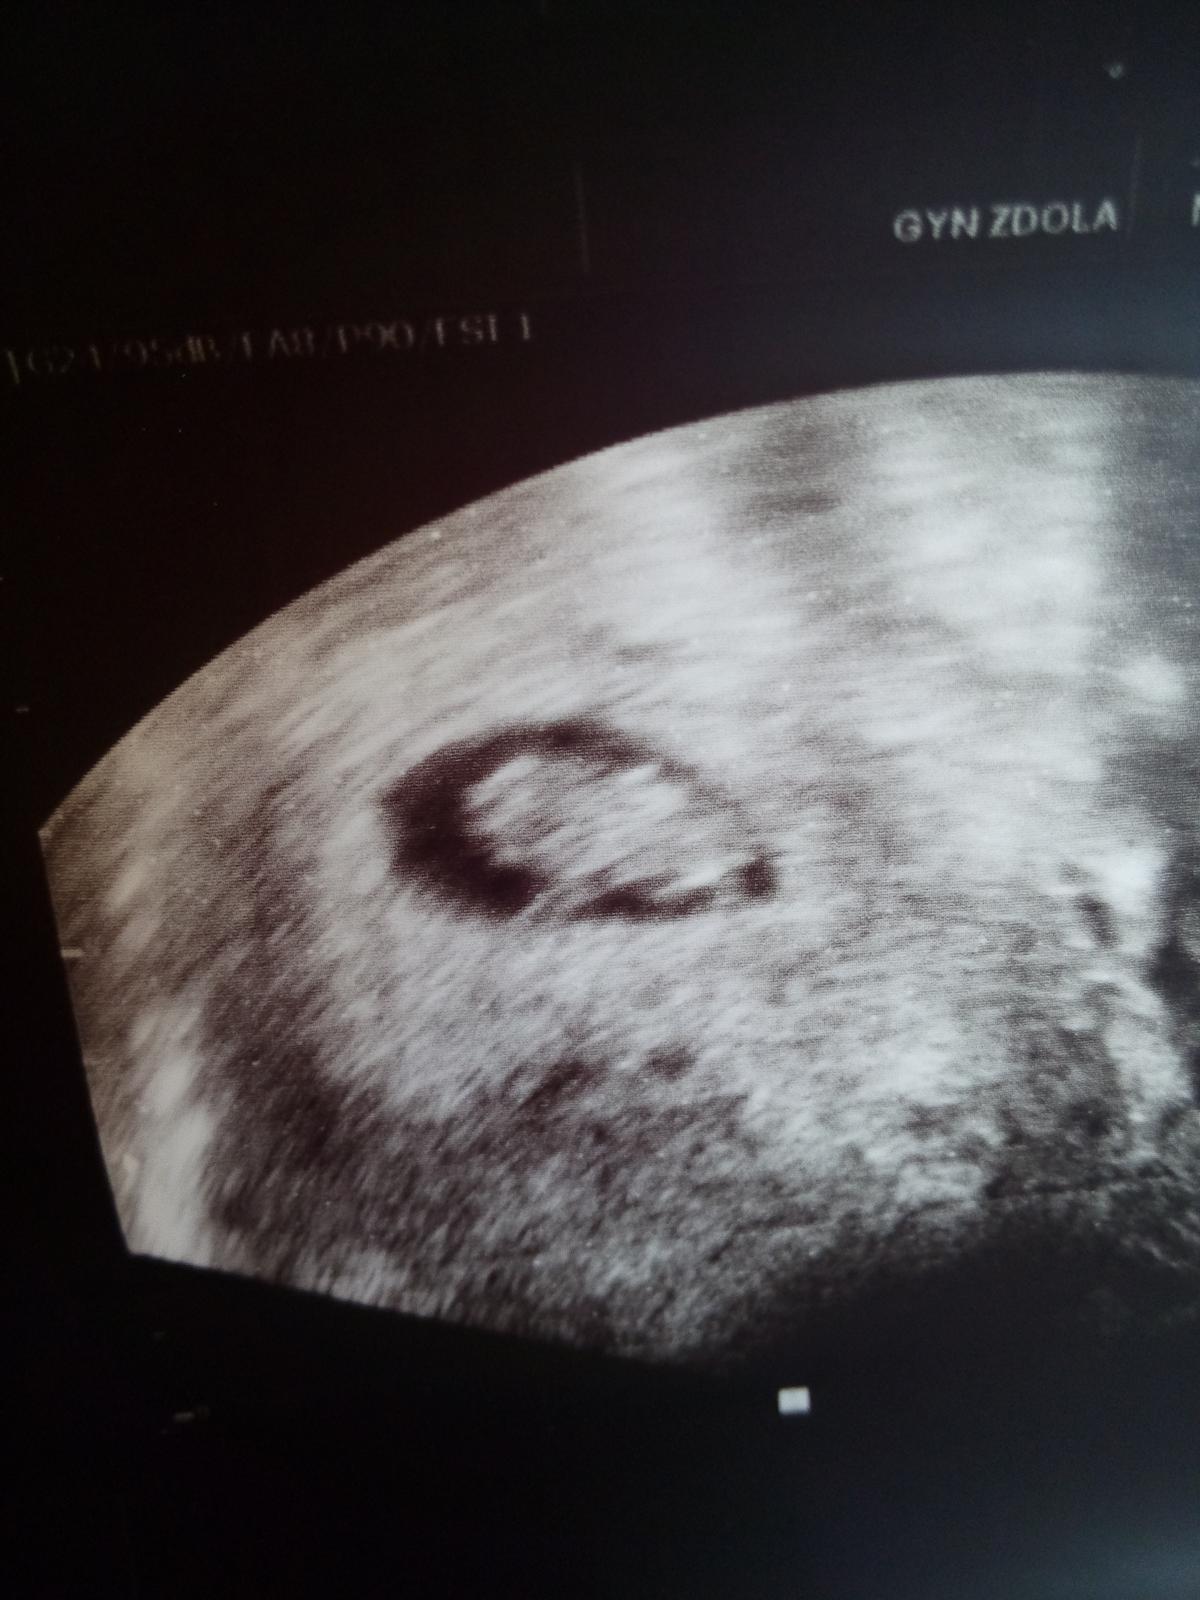

Ahoj holky, tak jsem dneska byla u Dr. a potvrdila mi miminko! Jsem teprve v 6 tydnu, srdicko jsme jeste nevideli, tak jdu pristi tyden znova, tak snad jej uvidime. Boze ja jsem stastna!! 🙂 Moc Vam vsem dekuji za podporu. :-*